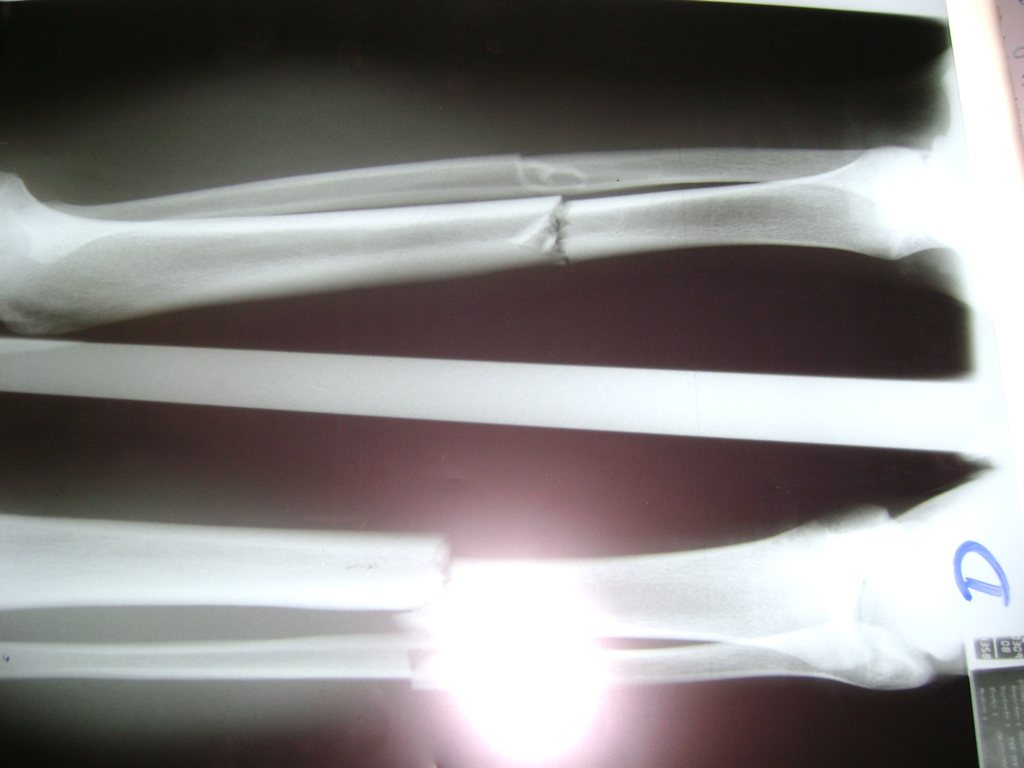

Cirugias en El Salvador - Perone y Tibia

Aunque cada uno de estos huesos puede fracturarse por separado, normalmente la rotura es una lesión que se produce de forma conjunta

La mayor parte de las roturas implican a la parte proximal del hueso (parte del hueso próximo a la rodilla) o a la parte distal (parte del hueso cerca del tobillo).

Debido a la fina cobertura de piel que recubre la tibia y el peroné, las fracturas generalmente son abiertas, es decir, el hueso roto rasga la piel, atravesándola. Las fracturas de tibia y peroné generalmente se producen por un fuerte impacto o torsión.